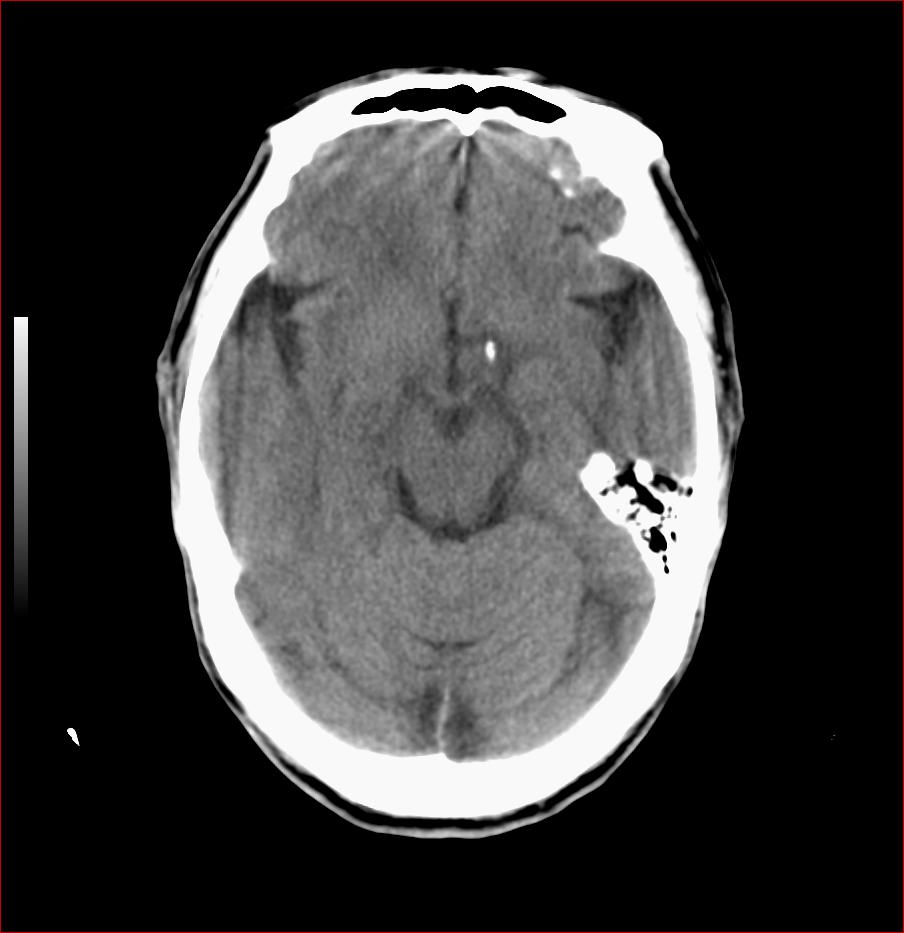

男,84岁,左下肢无力伴口角歪斜1天,血压160/80。请问一下双侧基底节区是脑梗塞吗?

基底节区脑梗塞,脑萎缩,左侧小脑脑梗塞

右侧基底节区斑片状低密度影,边缘模糊,结合临床考虑:1.右侧基底节区脑梗塞;2.老年性脑改变。

1.两侧基底节区及右顶深部脑梗塞。2.右侧外囊区脑软化灶。3.脑萎缩。4.脑白质脱髓鞘改变。

右侧基底节区斑片状低密度影,边缘模糊,结合临床考虑:1.右侧基底节区脑梗塞;2.老年性脑改变

1.双基底节区及双顶深部脑梗塞;2.右外囊区软化灶;3.皮层下动脉硬化性脑病.

1 两侧基底节区脑梗塞;

2 右侧壳核区脑软化灶;

3 脑白质脱髓鞘;

4 脑萎缩。